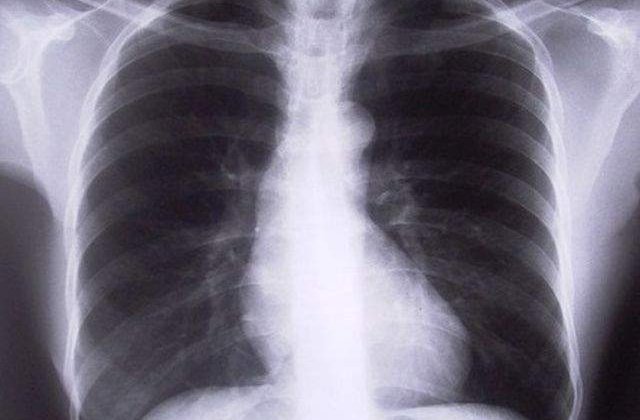

9AM.ro va prezinta cateva alimente pe care ar trebui sa le evitati in cazul in care aveti astm sau pentru a va proteja un organ foarte important: plamanii.